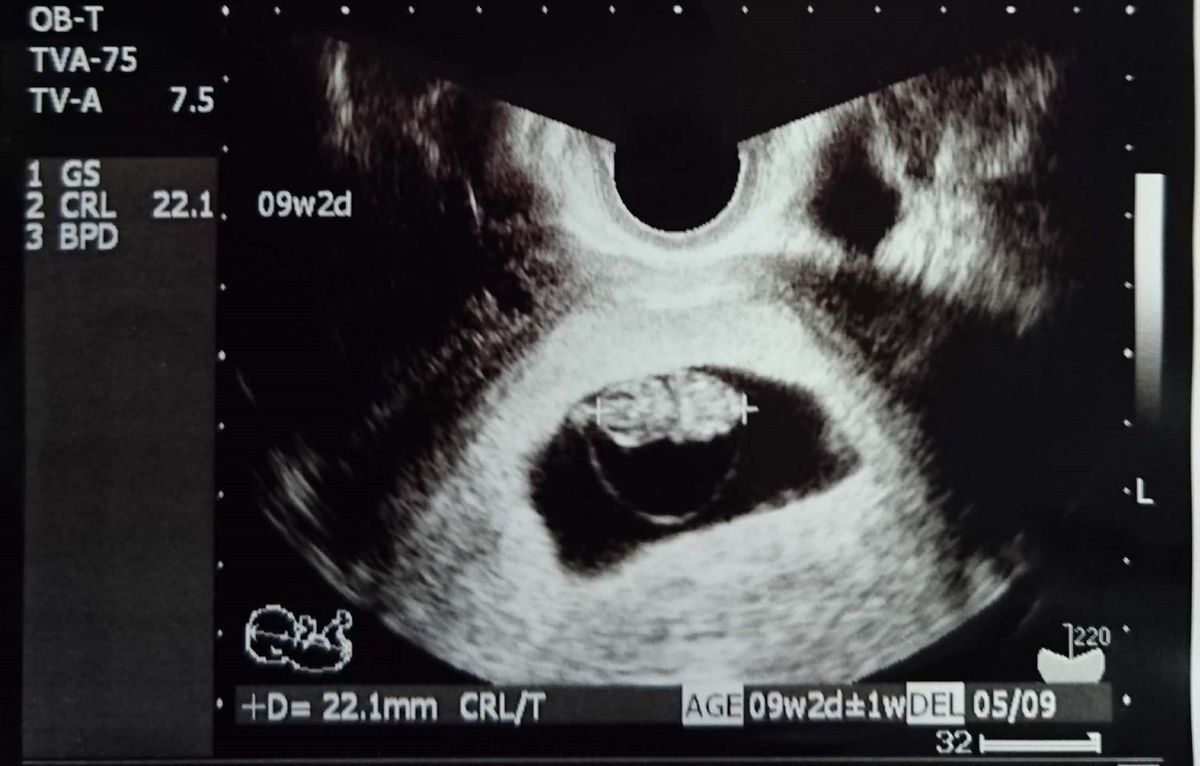

第9週のエコー写真 心拍を確認後、順調に大きくなってきた

CRL:22.1mm

胎嚢がぐっと大きくなり、頭と胴体が分かれています。左の丸い部分が頭で、右が胴体のようです。ようやく、「母子手帳をもらってきて」と言われましたが、やはりすぐには受け取りに行けませんでした。だんだんとつわりがひどくなり、空腹時は胃がムカムカし、食べると気持ち悪い状態が続きました。お腹の張りと、めまいがあったのもつらかったです。